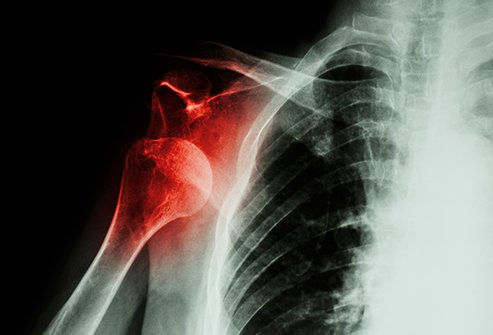

Above is the X Ray of his horrible injury

Indianapolis, IN- After miraculously recovering from being shattered into glass a month ago, Wentz has once again been reinjured. Carson Wentz's latest injury appears to be the result of fans doubting his recovery from not only his 2020 season in Philadelphia but his recovery from the injuries that took place after. Apparently, all the doubting and pressure caused Wentz to develop a blister- a shoulder hemorrhoid if you will, which doctors have labeled a chip. This " chip" in his shoulder could delay his colt debut for up to 8 more weeks. A sad turn of events for the Colts fanbase, who is already sick of him.